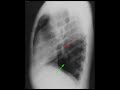

This is a 19 year old male presenting with cough. Frontal and lateral radiographs of the chest were obtained. Initial evaluation of the frontal radiograph demonstrates asymmetric inflation of the lungs, with the right lung appearing less expanded than the left lung. The right lung is hypoinflated. Additionally, the red arrow points to a vertically oriented tubular structure. On the lateral radiograph, this tubular structure is again identified by the red arrow. The green arrow corresponds to a hyperlucent left lower lobe secondary to compensatory hyperinflation. Findings are consistent with Scimitar syndrome. The term "Scimitar" refers to the fact that the vertically oriented tubular structure resembles the Turkish sword known as a scimitar. In this condition, a portion of the right lung is hypoplastic and is drained by an anomolous vertically oriented pulmonary vein. Most commonly, this vessel drains into the inferior vena cava instead of the left atrium.